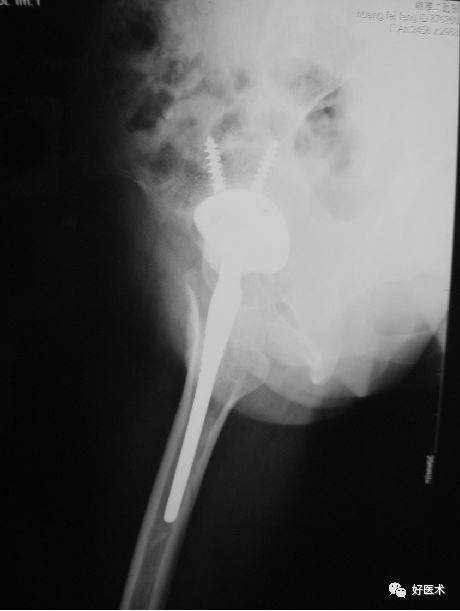

患者,男,69岁,因“摔伤致左髋部疼痛伴活动受限3小时”为主诉于今年10月12到我院急诊科就诊。急诊行X线片检查示:“左侧股骨颈骨质连续性中断”。

入院查体:

-

T:36.5℃ P:80/min R:18/min BP:135/80mmHg;

患者神志清楚,精神可,心肺腹查体未及明显异常。脊柱无畸形,骨盆挤压试验分离试验阴性,右下肢呈短缩外旋畸形,外旋约40°,较健侧肢体短缩约2cm。右髋部稍肿胀,无明显的瘀斑。右侧腹股沟中点压痛阳性、轴向叩击痛阳性。右侧Bryant三角底边较健侧短缩。膝关节、踝关节活动尚可无压痛,趾端感觉正常,余肢体未及异常。

Garden分型?

Ⅳ型

内固定 OR 髋关节置换?

髋关节置换

全髋 or 半髋?

股骨头置换

骨水泥 OR 非骨水泥?

非骨水泥假体